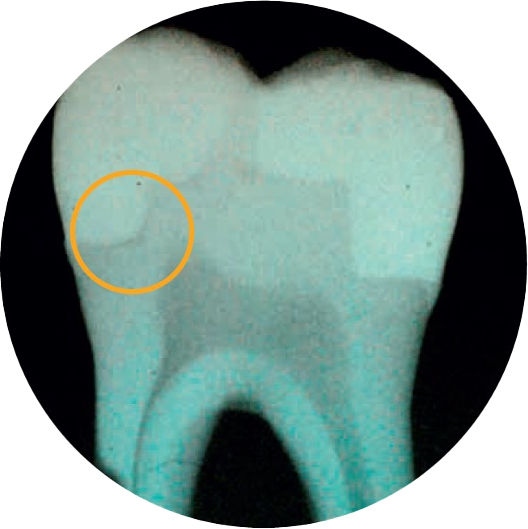

Sei incerto sulla formazione di spazi vuoti?

Secondo due odontoiatri su tre, l’adattamento della cavità è l’attributo più importante per un restauro ottimale.4

Il materiale SDR flow+ rappresenta una svolta unica nel suo genere nel settore odontoiatrico. Si tratta di un fluido bulk-fill che combina esclusive proprietà autolivellanti e il migliore stress da contrazione della categoria, che consente il posizionamento fino a 4 mm con un eccellente adattamento della cavità, per un posizionamento di restauri privo di spazi vuoti.